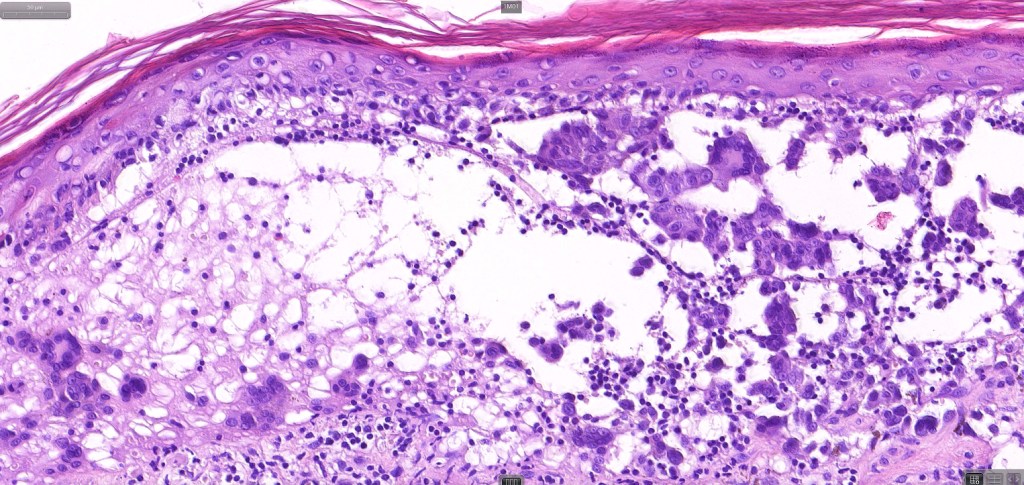

An exceedingly rare variant of melanoma. The term includes cases of melanoma that show features of an associated inherited bullous dermatosis such as epidermolysis bullosa or acquired immunobullous intraepidermal or sub epidermal bullous dermatosis such as pemphigus or bullous pemphigoid and cases where the blister develops directly overlying the melanoma in the absence of any underlying/associated blistering condition. It is generally recommended that measurement of the melanoma should be from taken below the blister/vesicle so as to avoid over-estimating tumor thickness.

Case courtesy of Dr. Antonina Kalmykova